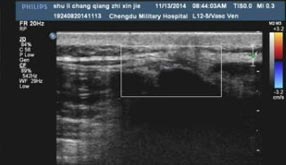

2018年,成都风湿医院率先从意大利引进肌骨超声,并获得该仪器检测在西南地区的临床应用授权资格。

肌骨超声(musculoskeletal ultrasound,MSUS)技术是通过高频超声(3~17Hz)扫描提供优异的临床图像,以清晰显示肌肉等软组织层次关系及其内部机构来诊断肌肉骨骼系统疾病的新型超声检查技术。通过肌骨超声,医生可以分辨毫米级以下动态的这些组织结构肌肉、肌腱、韧带、关节囊、关节面及周围神经等浅表软的毗邻关系、形态大小、结构纹理、血流分布,从而获取这些组织器官的解剖变异、炎症、退行性病以及创伤等病变的全方位信息,从而对疾病进行精准评估。